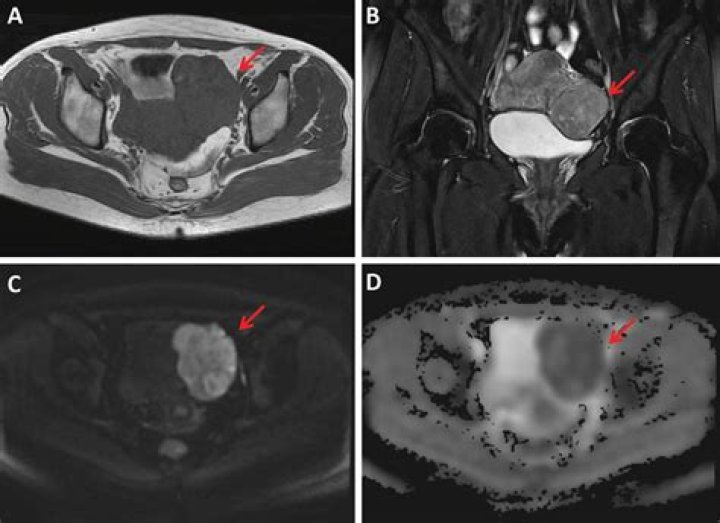

Can MRI tell if fibroid is cancerous?

Magnetic resonance imaging MRI scans can help tell if a uterine tumor looks like cancer, but a biopsy is still needed to tell for sure.